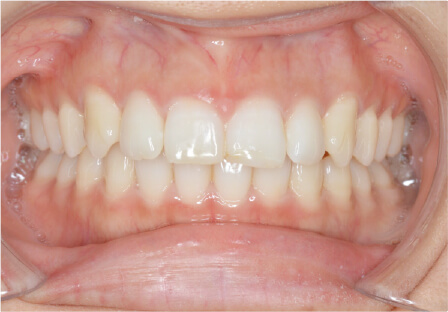

過蓋咬合の症例

15歳

/

女性

相談内容

前歯と前歯が噛んでいない

カウンセリング・診断結果

過蓋咬合

治療内容・方法

全額アライナー矯正

術後の経過・現在の様子

クリアライナー使用

治療のリスク

痛み・歯根吸収・歯肉退縮・虫歯・後戻り

費用・治療期間

830,000円、2年